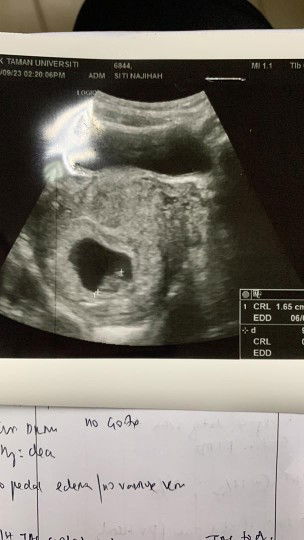

tadi pagi pergi scan baby dekat kk. dr bagitau saiz baby kecik berbanding usia kandungan. kandungan dah 10 minggu, tapi saiz baby tepat 8 minggu je masa scan kat kk. sbbkan hati dah risau sangat, td pergi private clinic untuk double check sekali lagi. alhamdulillah, scan dekat private nampak baby lebih jelas dan saiz baby pun dah 9 minggu. dr ckp baby suka main sorok sorok. tu yg susah nak ukur saiz. semoga baby terus membesar dan sihat sihat je. #firstbaby #firstmom #1st_pregnacy